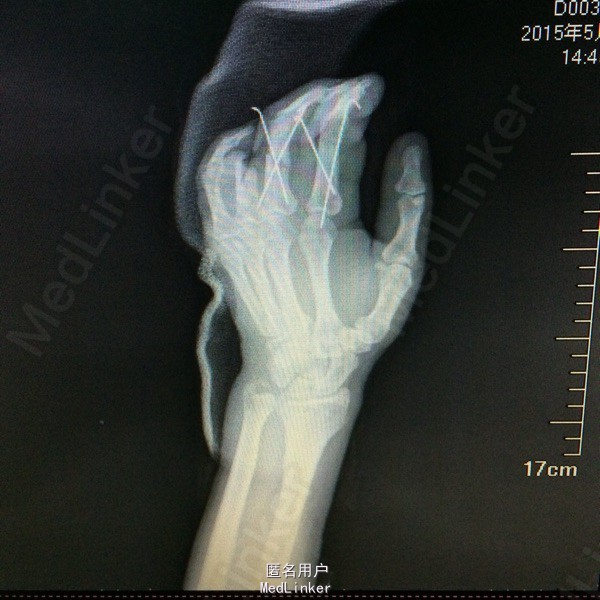

体格检查:T:36.3°,P:80bpm,BP:120/75mmHg,R:20bpm。神清皮肤巩膜无黄染,浅表淋巴结未及。头颅形状无畸形,口唇无紫绀,气管居中。双肺呼吸音清,未闻及干湿罗音。HR:80bpm,心律齐,各心脏听诊区未闻及明显病理性杂音。腹部平软,无压痛及反跳痛。生理反射存在,病理反射未引出。 专科检查:左手2-5指指根部环形伤口,伤口不规则,皮下组织部分分离,左手2-5指少许畸形,局部触痛明显,伤口以远灰色,无血供,感觉消失,关节屈伸活动受限。 辅助检查:2015-5-12日我院X片检查提示:左手及2、3、4近节指骨粉碎性骨折;左腕游离骨片影,考虑陈旧性外伤所致,请结合临床。(D00300044)。

初步诊断:左手2-5指压伤不全离断 治疗计划:1、完善相关检查及术前准备:心电图,血常规,尿常规,肝肾功能电解质、术前全套等。 2、臂丛麻醉下行再植术。 3、术后“三抗”治疗,烤灯保暖。再植术 左手2-4指骨折复位交叉克氏针固定,

左手2-4指骨折复位交叉克氏针固定,透视检查骨折复位固定良好;患者诉伤口轻度疼痛,无发热症状。查体:伤口无异常分泌物,手指血供良好,手指屈伸受限。主任医师查房查房看过病人,患者术后第10天,拟明日出院,嘱定期伤口换药,门诊随诊。 请问各位专家,术后多久康复锻炼效果最好,?怎么预防坏死?